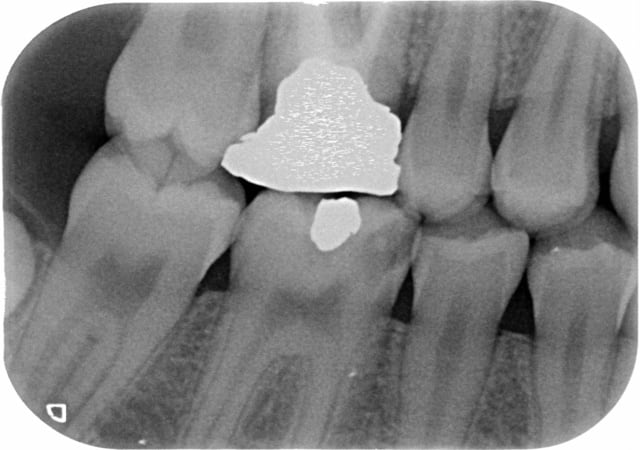

Je voudrais votre avis car j'ai une patiente de 13 ans qui a de nombreuses caries et qui a déjà la 16 dévitalisé avec un très gros amalgame dessus ( il reste vraiment rien de la dent).

Peut-on faire un Inlay-core sur cette dent avec une Couronne provisoire le temps qu'elle finisse sa croissance puis une CCM? ou bien je n'attend pas pour la CCM ?

pourquoi pas,bien que j'ai laissé tomber les IC (trop vu passer de fractures de racines et grâce aux progrès du collage on peut faire autrement) mais j'aimerais bien voir la radio en entier et l'apex de la dent

d'autre part,depeches toi de soigner 36 déjà limite coiffage avant de te retrouver à faire le traitement et comble ts les sillons des 6 et 7 apparemment très anfractueux au vu du BW